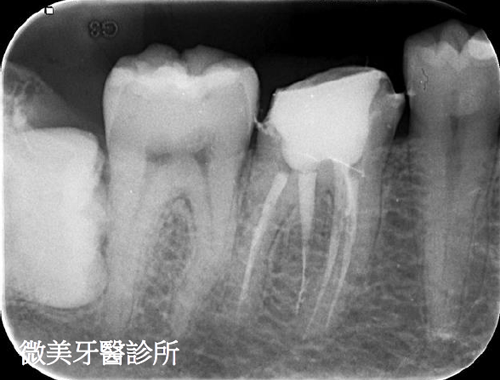

根管鈣化阻塞,利用顯微鏡搭配器械完成多根管治療

原先根管治療未完整,利用顯微鏡重新根管治療,達到多根管封填